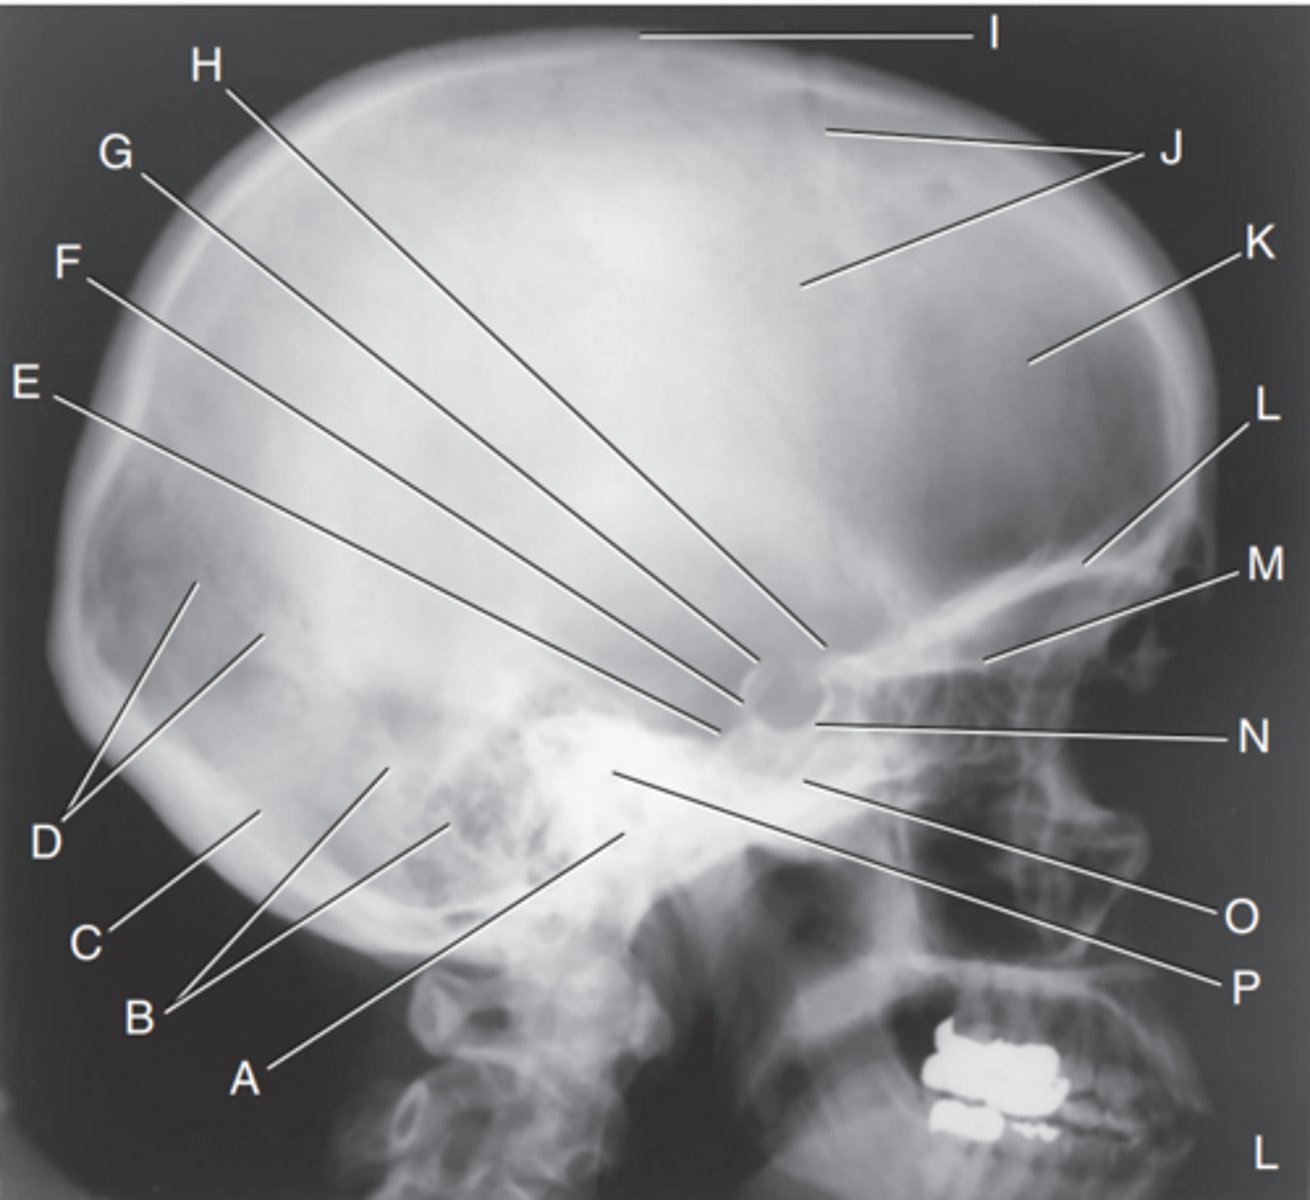

EAM

Label A

Mastoid portion of temporal bone

Label B

Occipital bone

Label C

Lambdoidal suture

Label D

Clivus

Label E

Dorsum sellae

Label F

Posterior clinoid processes

Label G

Anterior clinoid processes

Label H

Vertex of cranium

Label I

Coronal suture

Label J

Frontal bone

Label K

Orbital plates

label L

Cribriform plate

Label M

Sella turcica

Label N

Body of sphenoid (sphenoid sinus)

Label O

Petrous portion of temporal bone

Label P